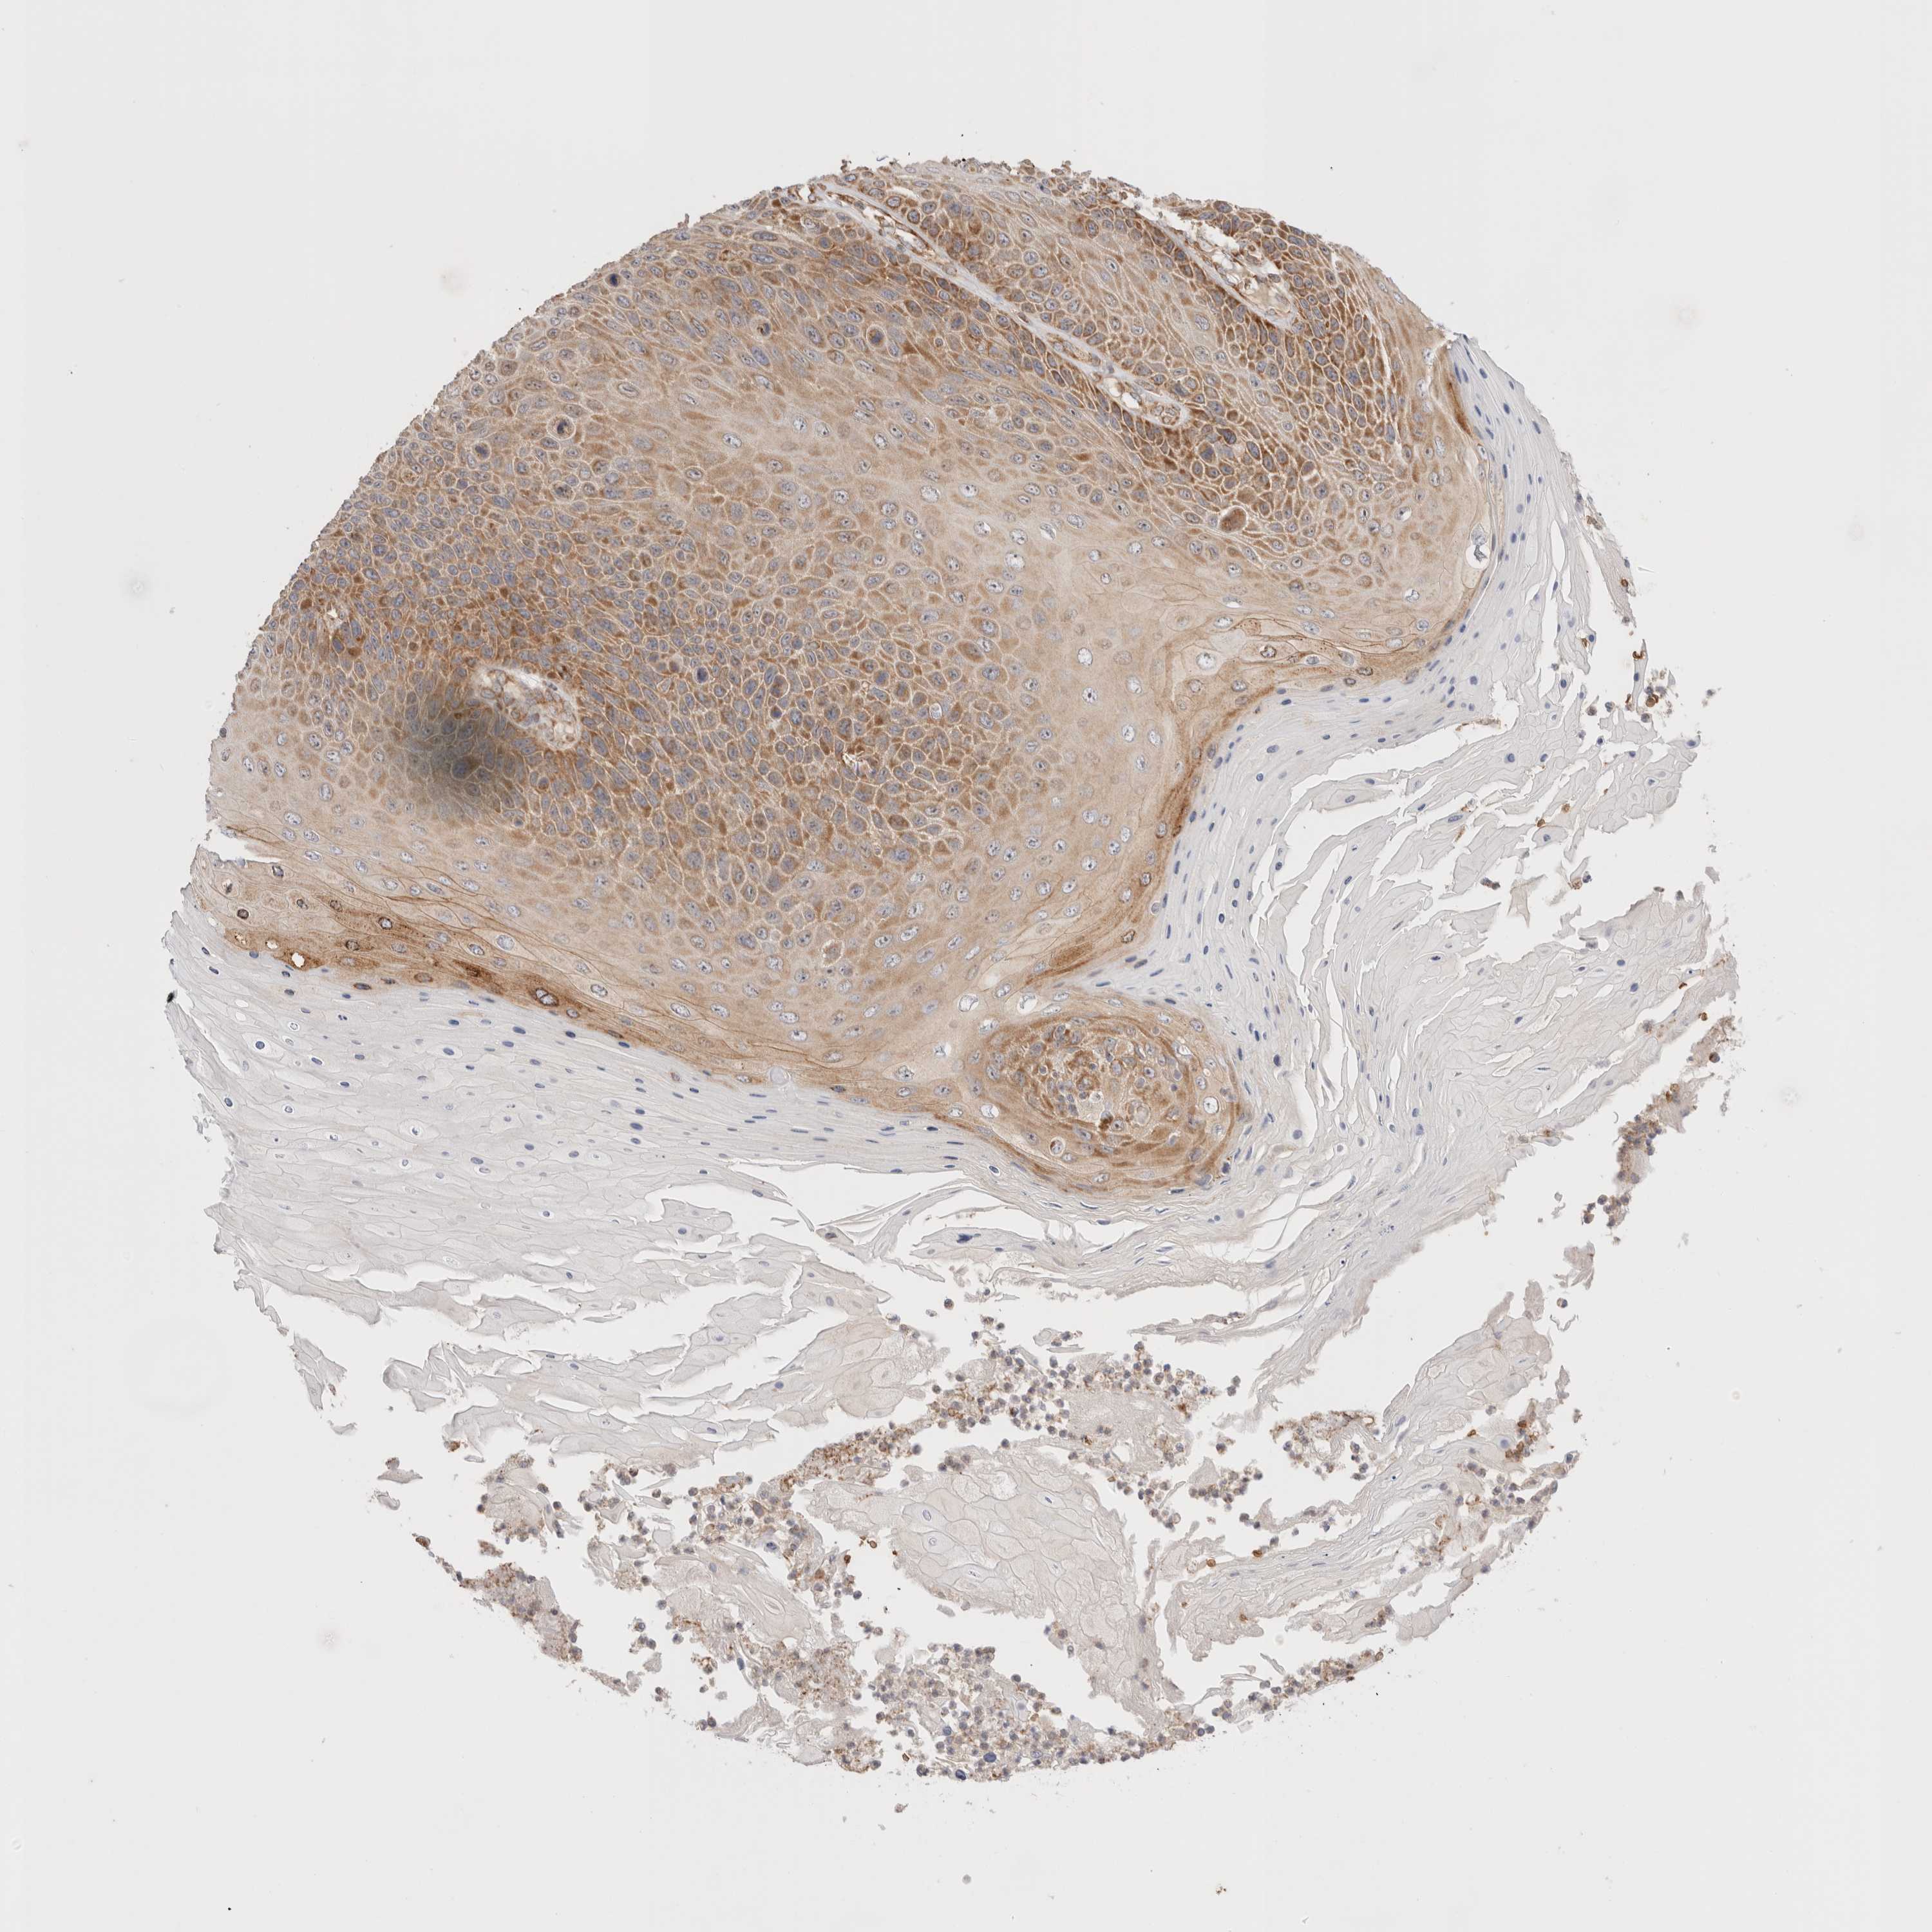

CANCER SKIN CANCER Show tissue menu

Basal cell and squamous cell cancer

SKIN CANCER - Protein expressioni

A mouse-over function shows sample information and annotation data. Click on an image to view it in a full screen mode. Samples can be filtered based on level of antibody staining by selecting one or several of the following categories: high, medium, low and not detected. The assay and annotation is described here.

Each image is clickable and will lead to virtual microscopy that enables deeper exploration of all samples and also displays staining intensity scores, fraction scores and subcellular localization as well as patient and tissue information for each sample.

Antibody HPA026992

Staining

High

Strong

Quantity

Location

Basal cell carcinoma

Squamous cell carcinoma, NOS

Squamous cell carcinoma, metastatic, NOS